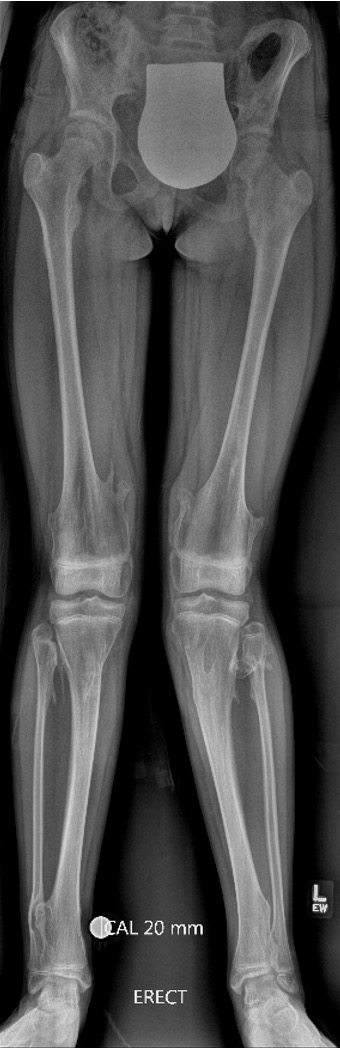

Lower limbs

- mildly short stature

- eg length discrepancies

- valgus knees / valgus ankle

Knee - genu valgum

Genu Valgum OCMultiiple OCMultiple OC

Knee

Incidence

Clement et al Knee 2014

- 172 patients with HME

- 90% had exostosis around the knee

- 20% had valgus deformity

- 15% had FFD deformity